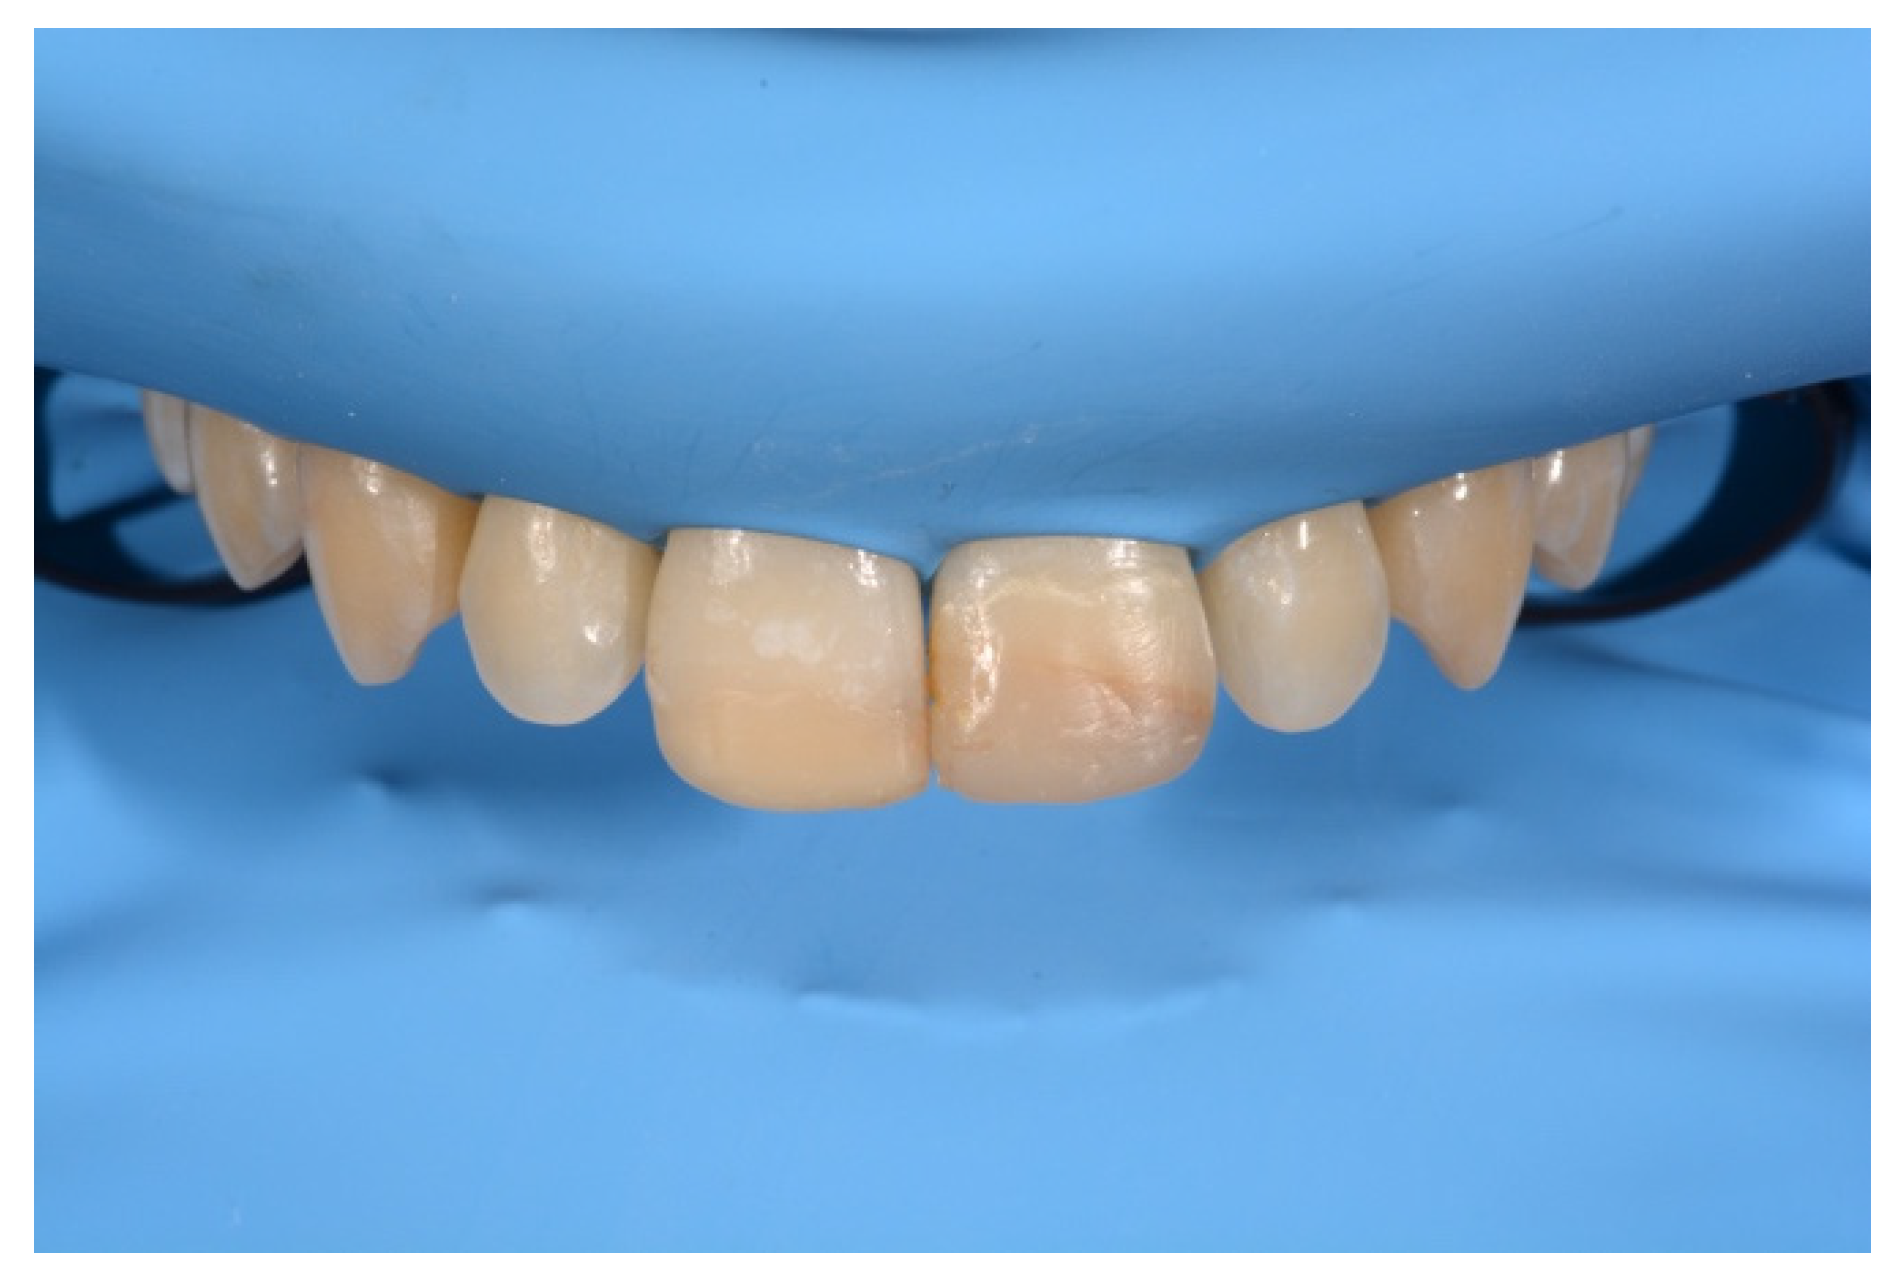

2. Case Presentation